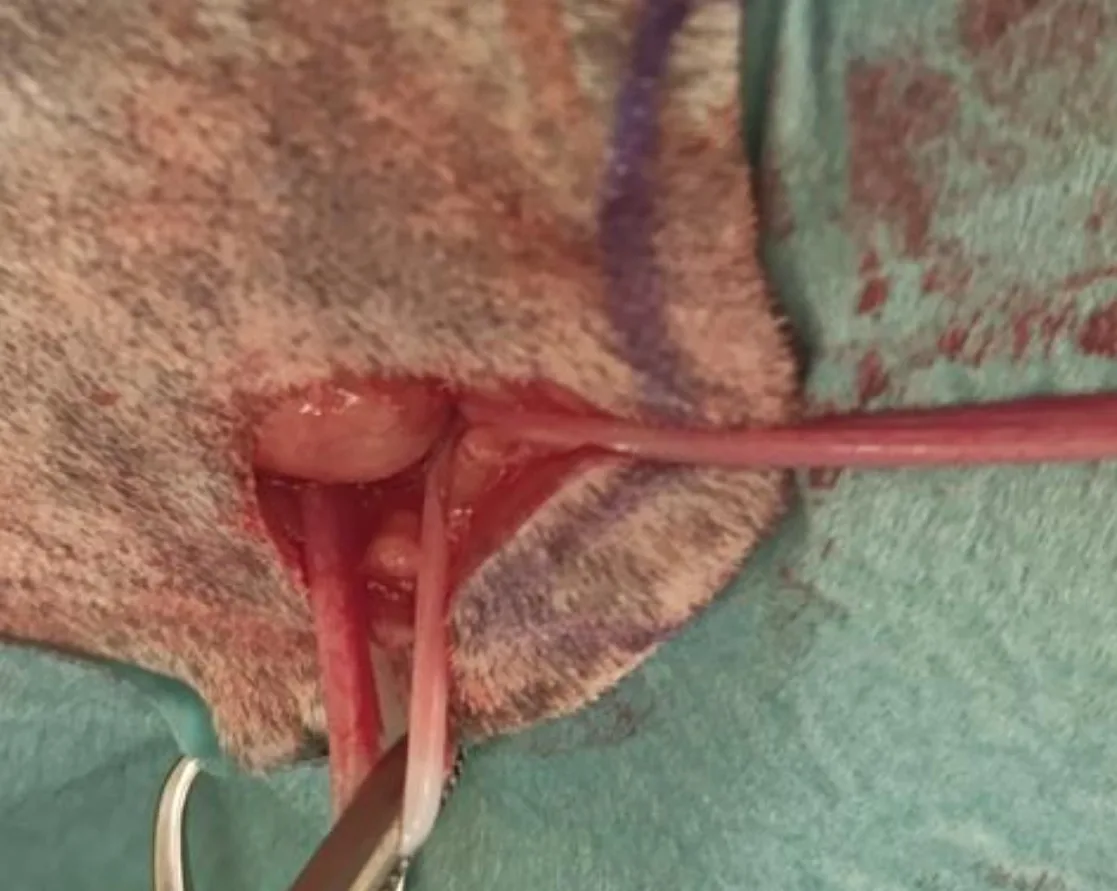

Step 4: Ligate the Ovarian Pedicle

Identify and exteriorize the left uterine horn and ovary via digital palpation or a spay hook.

Create a hole in the mesovarium, then place 1 straight and 1 curved Halsted mosquito forcep across the ovarian pedicle ≈1-cm dorsal to the ovary. Apply 2 ligatures using a 2-0 absorbable monofilament suture on the ovarian pedicle, which should then be transected between the hemostats.

Author Insight

A spay hook can be useful for externalizing the reproductive organs through small incisions.